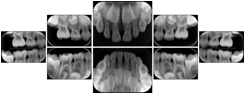

Intra-oral radiography typically involves acquisition of multiple images of various parts of the dentition. Many digital radiographic systems offer customized templates that are used for displaying the images in a study on the screen. These templates may also be referred to as mounts or view sets. The Structured Display Object represents a standard method of encoding and exchanging the layout and intended display of Structured Displays. A structured display object created in this manner could be stored with a study and exchanged with images to allow for complete reproduction of the original exam.

In most standard cases, images are oriented in structured layouts. These structured displays are useful to be shared between providers for reference purposes.